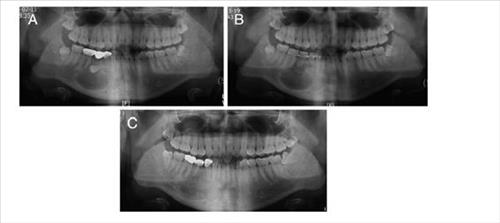

°³²¼¼ºê¶õ½ºº´¿ø ÀÇ·áÁø, ¼ö¼ú °á°ú Àú¸í ÇмúÁö¿¡ (¼¿ï) Àü¸íÈÆ ±âÀÚ = ±¹³» ÀÇ·áÁøÀÌ Ä¡¾ÆÀÇ ¸Åº¹ »óÅ ¶§¹®¿¡ ÀÕ¸ö»À°¡ °ÅÀÇ ¾ø¾î Ä¡¾Æ À̽ÄÀÌ ¾î·Æ´ø ȯÀÚ¿¡°Ô ÀÚ°¡ Ä¡¾Æ¸¦ À̽ÄÇÏ´Â ¼ö¼ú¿¡ ¼º°øÇß´Ù. ÀÌ...